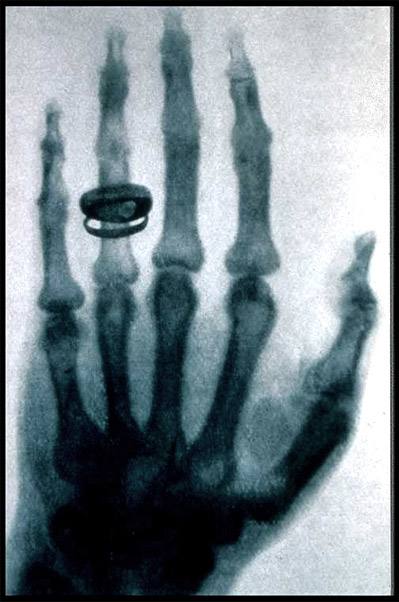

X射线是著名的伦琴发现的,它是影响医学的开端。X线发明的故事大家也都熟悉,伦琴在一个偶尔的机会下从X射线现中看见了自己手的骨骼。所以说X射线主要是用来看骨头。